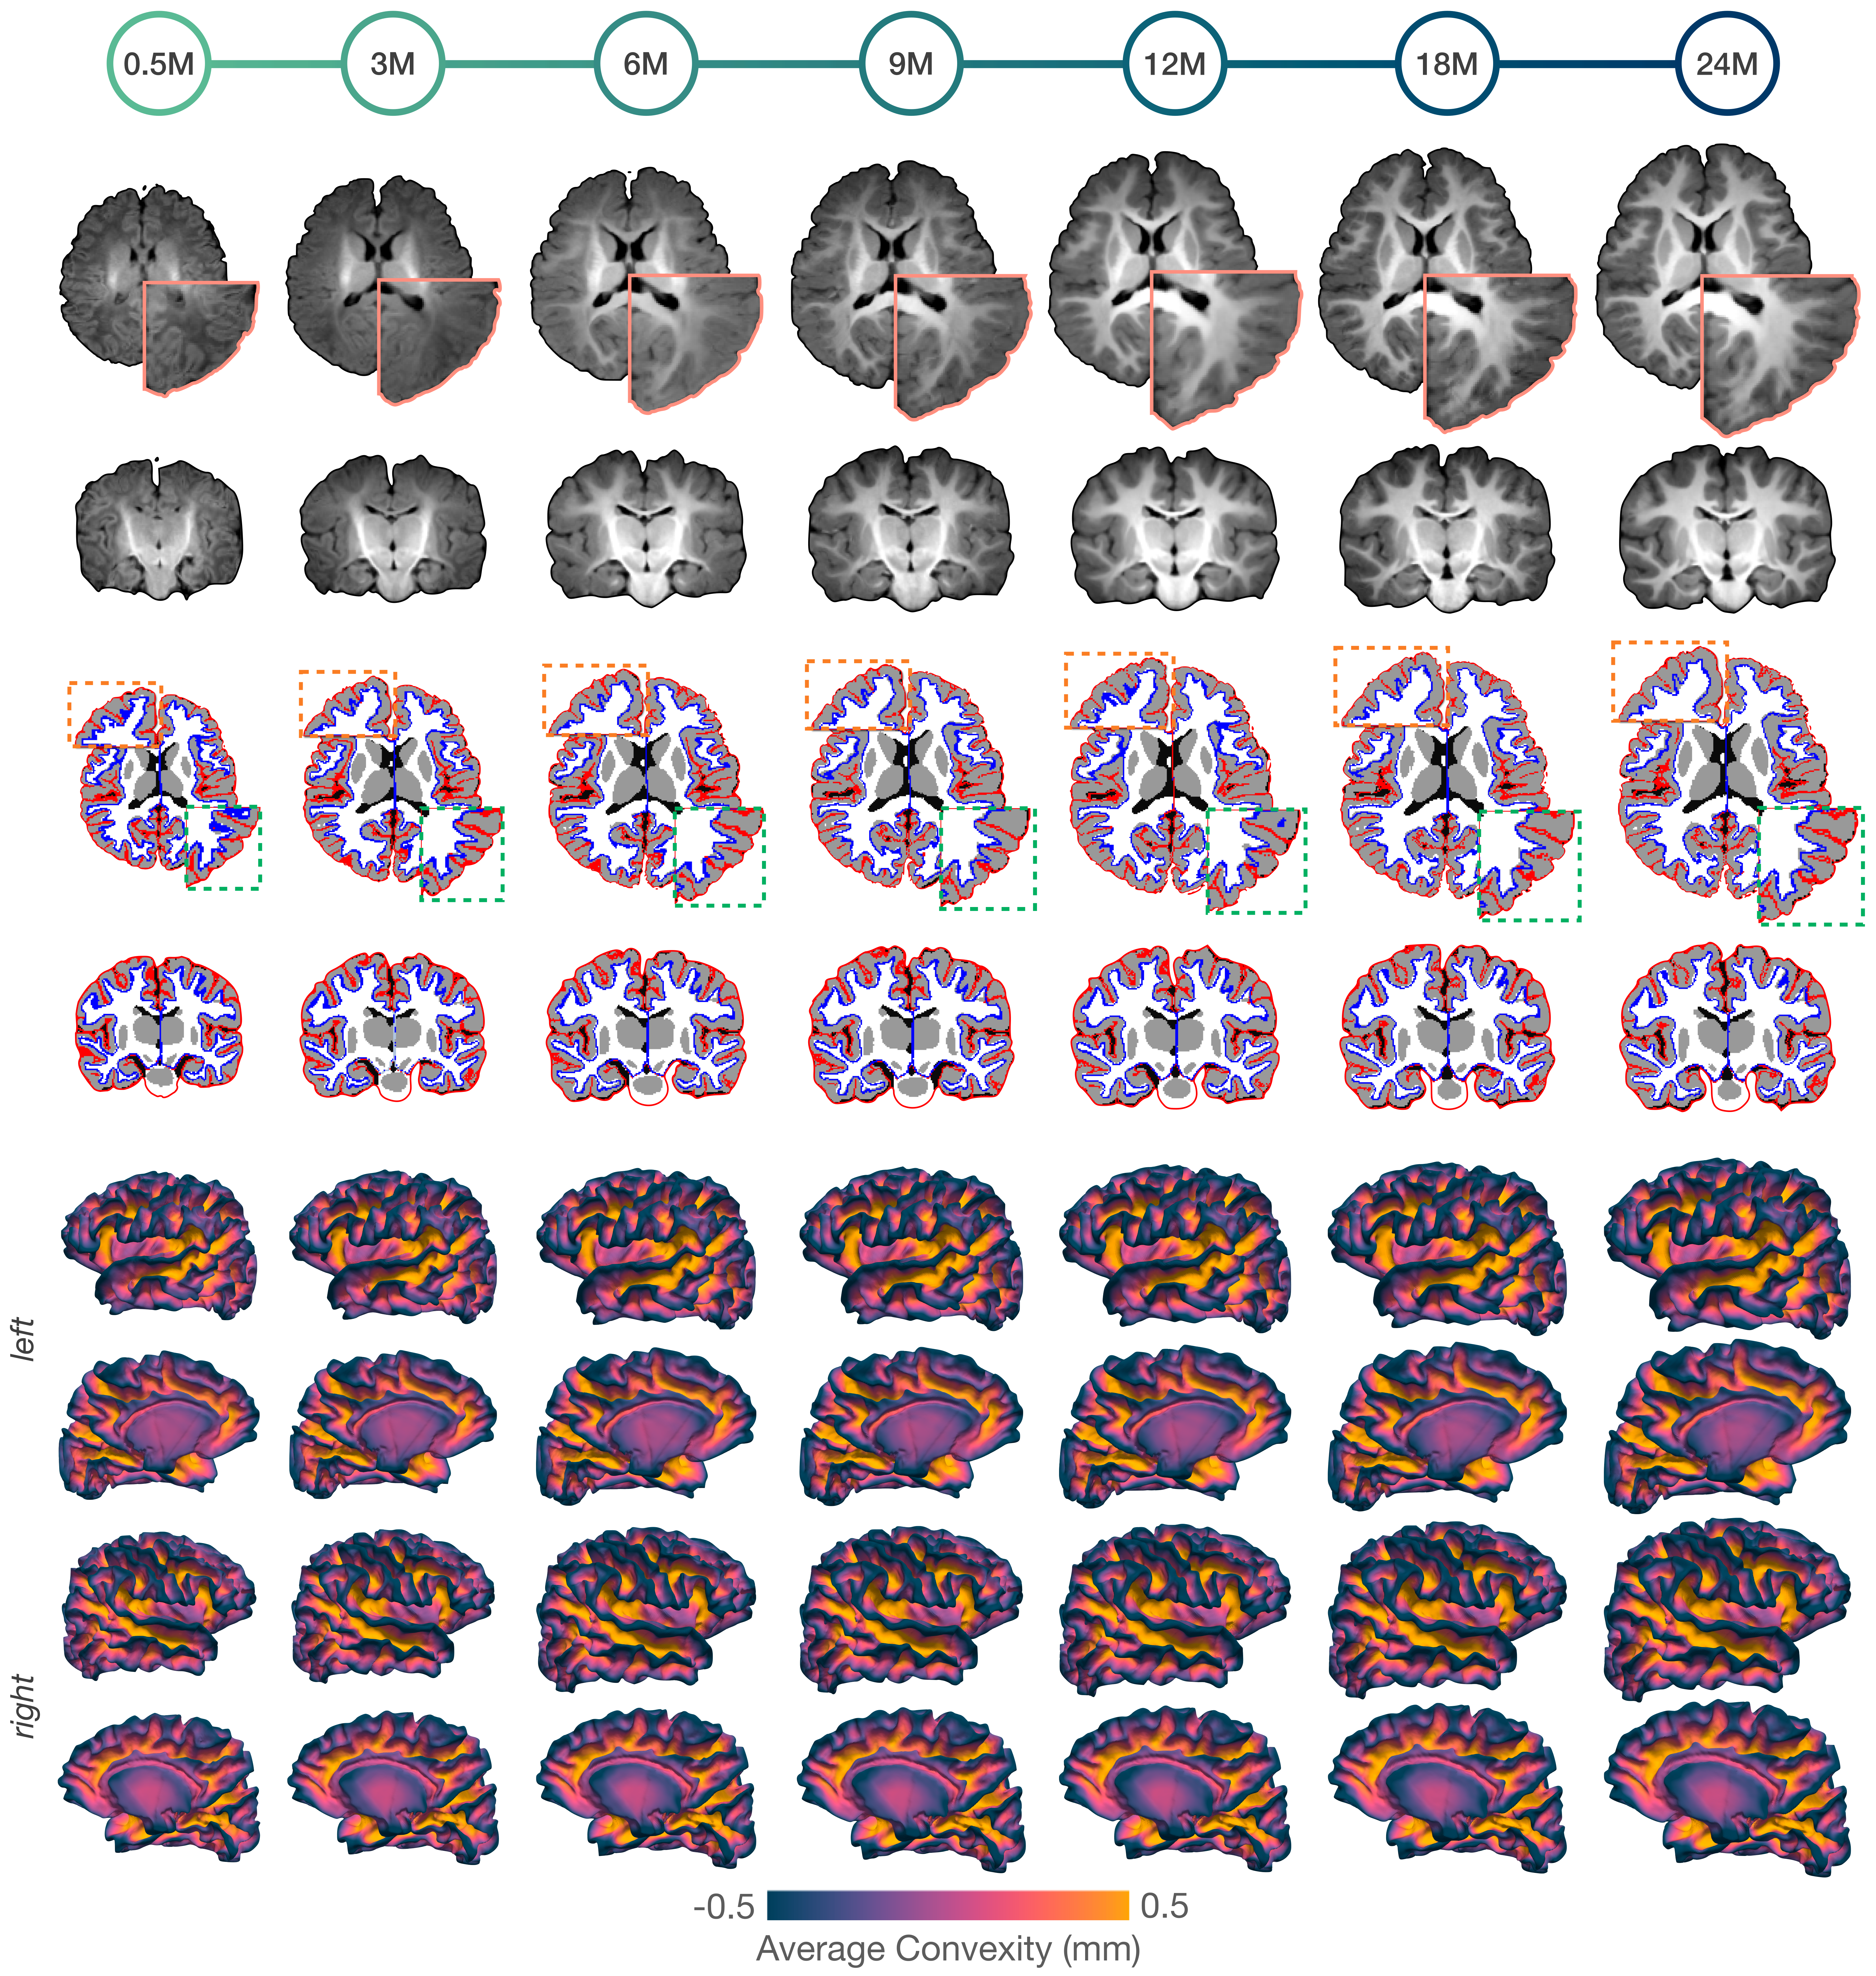

Our infant brain atlas (IBA) at each month faithfully captures the sulcal and gyral features of primary, secondary, and tertiary cortical folds (Figure 1), with developmental timing and left-right lateralization coherent with prior knowledge on early brain development. Our atlases preserve spatiotemporally heterogeneous trajectories of detailed folding and tissue features of the developing brain. Primary visual and motor cortices more developed during infancy experience less changes, in contrast to higher-order cortices that undergo delayed functional development associated with for example decision making, critical thinking, and reasoning.

Figure 1: Surface-volume atlases of the infant brain. Transverse and coronal sections of the T1-weighted atlases spanning 2 weeks to 24 months (top). White (blue) and pial (red) surfaces of the cortical atlases overlaid onto the brain tissue atlases (middle). Lateral and medial views of the white surface atlases colored by a geometric property called average convexity (bottom).